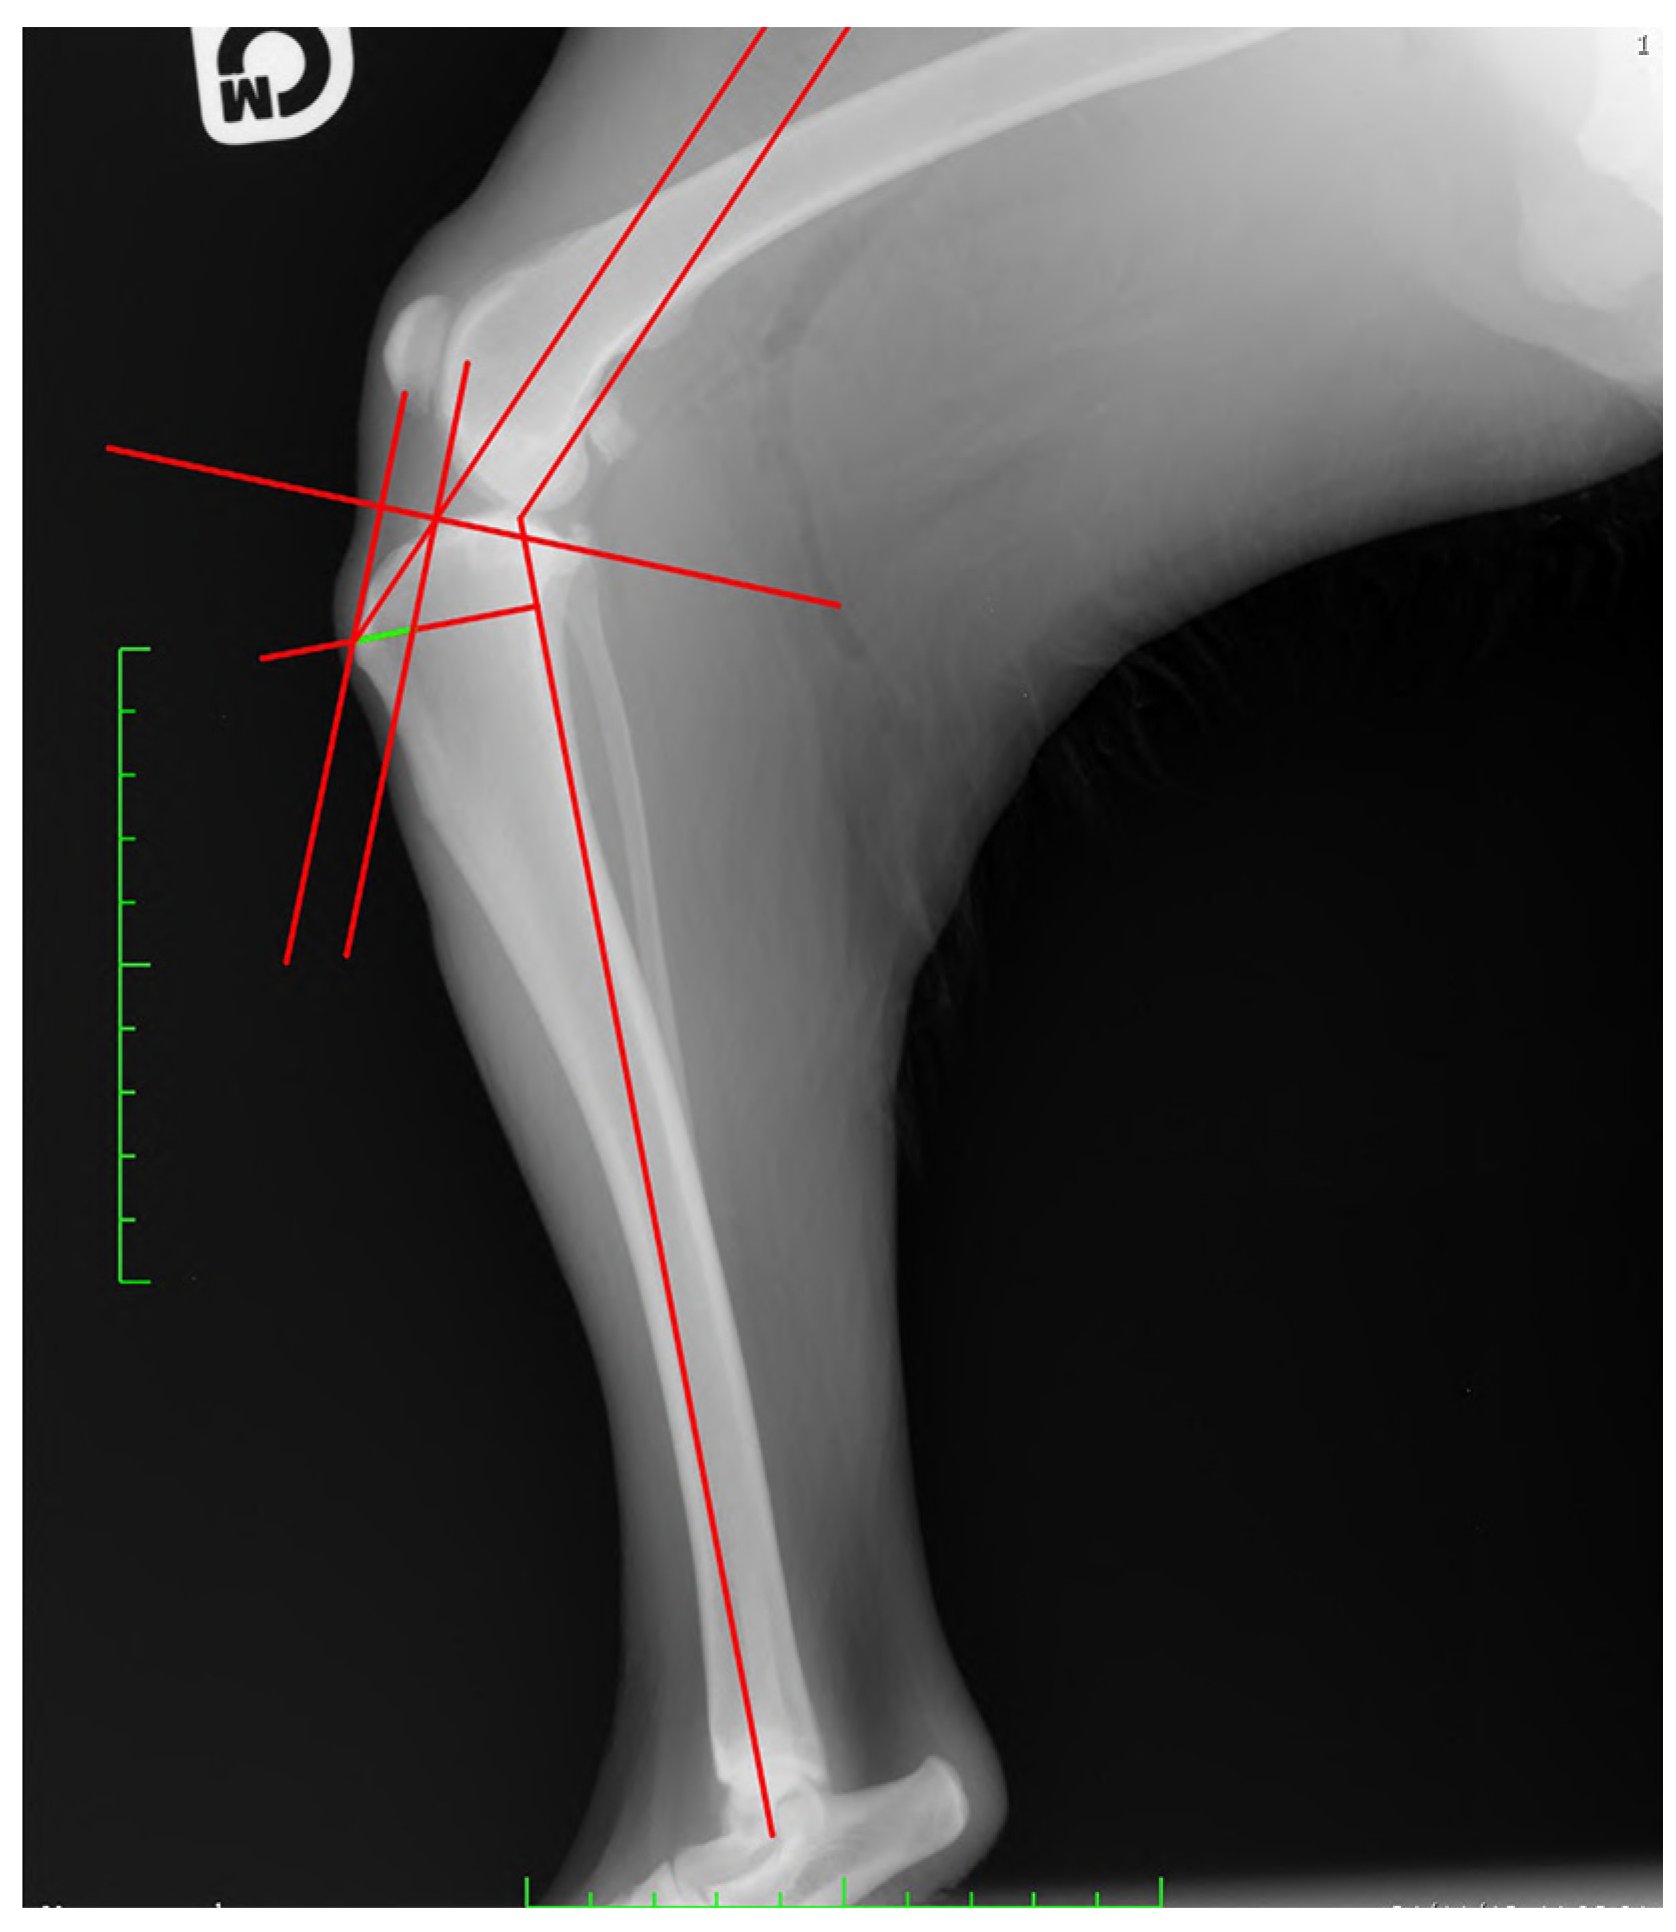

- For TAM, the tibial functional axis of the tibia, defined by a line joining the midpoint between the intercondylar tibial tubercles (in the stifle joint) with the center of the talocrural joint, was drawn. Then, the tibial plateau, defined by a line joining the points at the cranial-most and caudal-most edges of the medial tibial condyle, was drawn. Secondly, from the functional axis, a caudally directed 135° angle towards the femur was made. Next, a parallel line through the patellar insertion point on the tibial tuberosity was located. This line intersected the tibial plateau line that was previously drawn. A perpendicular line to the tibial plateau was placed starting from patellar insertion. Next, a parallel line through the intersection point was drawn. The distance between this line and the most-cranial point of the tibial tuberosity, measured along a line perpendicular to the function axis, was recorded as the required advancement [22] (Figure 2).